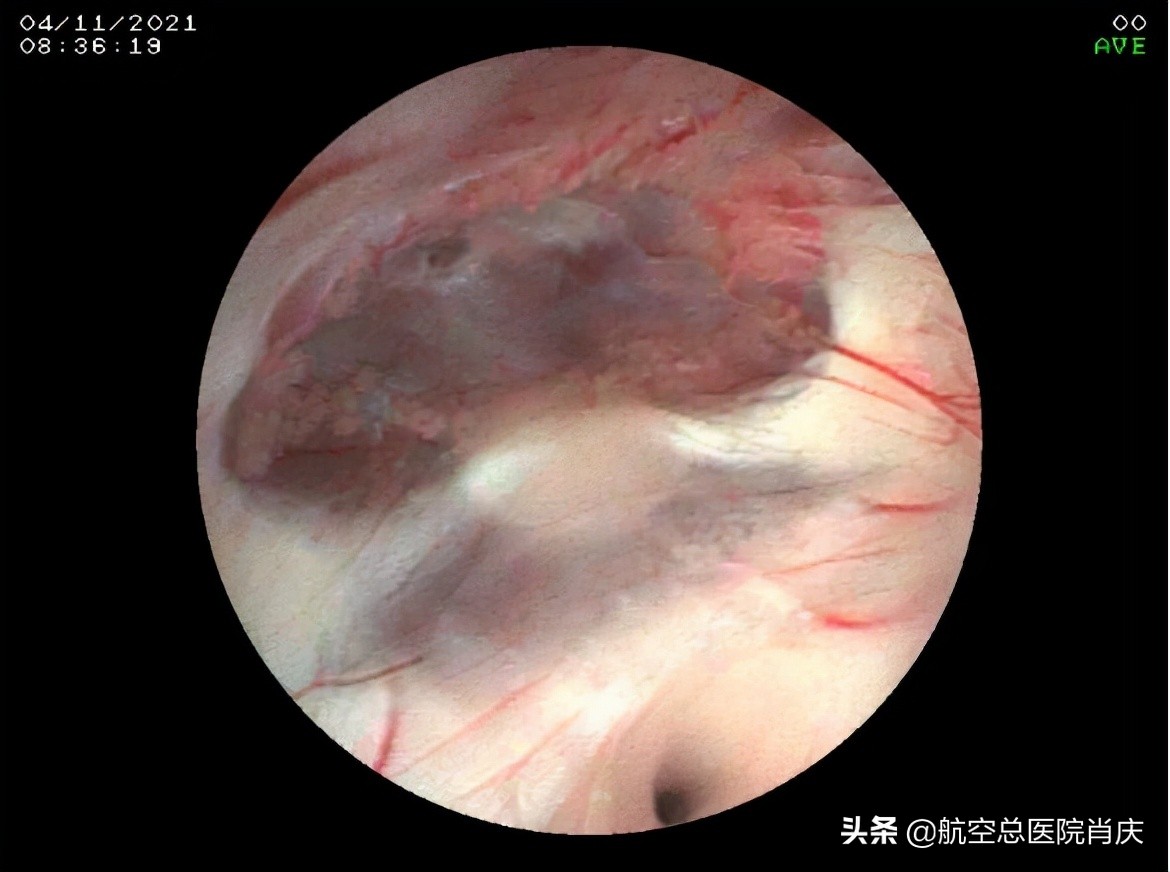

(完美的颅底动脉环

(探查第三脑室后部,四叠体池未见囊肿)